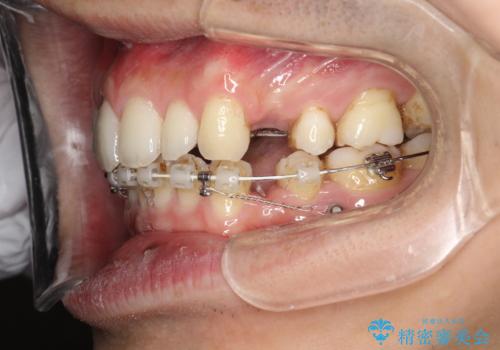

- 矯正装置

- ハーフリンガル

- 治療期間

- 2年6ヶ月

上下左右の歯を1本ずつ抜歯しして、上顎の前歯を後方に移動させるのと、正中の隙間を閉じる計画としました。

装置はなるべく目立たないものをご希望でしたので、ハーフリンガルを選択されました。